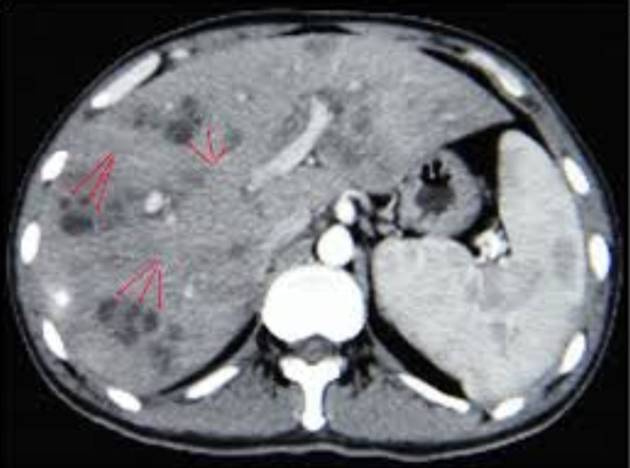

Hình 3